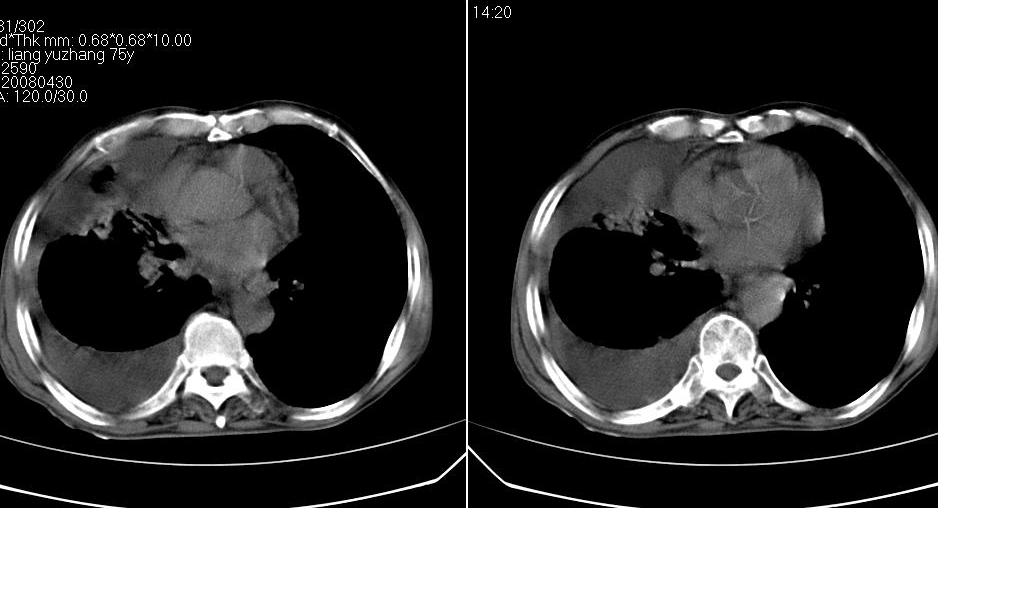

以下是引用zsl6918在2008-5-3 19:53:00的发言:[br]右肺中心型肺癌并纵隔淋巴结转移,胸膜转移,右肺癌性淋巴管炎。

以下是引用liuyue在2008-5-3 20:49:00的发言:[br]1.右侧中心型肺癌伴双肺转移瘤、纵隔淋巴结转移、右侧胸腔积液(侵及胸膜所致可能性大)。[br]2.右肺阻塞性肺炎,癌性淋巴管炎不除外。